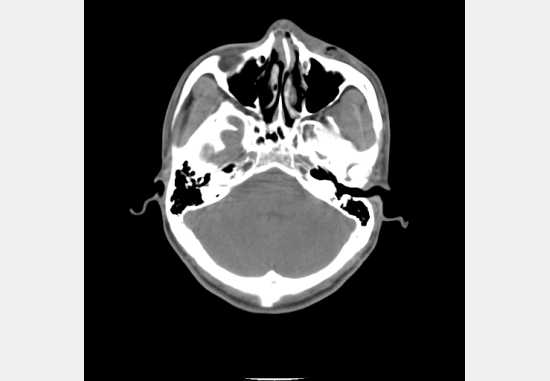

但是测试另一幅 还是不对 CT.dcm:

这幅图像看上去是CR的图,其实是CT序列图像里的一幅 ,因为是CT影像 所以要做值偏移处理 值=值×斜率+截距 这是高中学的,称为HU 至于为什么要这样我也不知道 dicom标准规定的 如果是CT图像需要进行偏移处理则进行偏移处理 然后进行窗值映射。